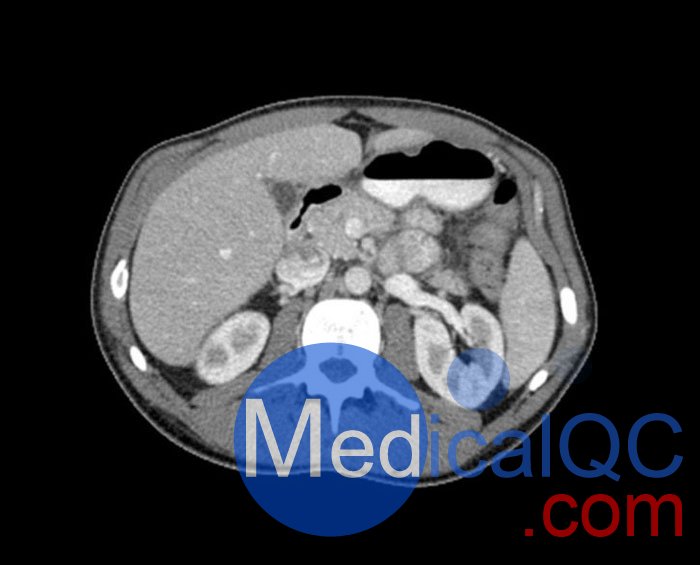

WEK57-01門靜脈期軀干模體,WEK57-01軀干模型模擬了門靜脈期的造影劑增強胸部、腹部和骨盆。它覆蓋了會陰的第二胸椎。

右側(cè)有髂淋巴結(jié)腫塊。

真實模擬脈管系統(tǒng)、骨骼和軟組織,包括肺、心臟、肝臟、膽囊、胰腺、脾臟、腎上腺、腎臟、胃、小腸、結(jié)腸、膀胱和前列腺。

右側(cè)髂外淋巴結(jié)腫塊。

WEK57-01門靜脈期軀干模體,WEK57-01軀干模型成像效果圖: